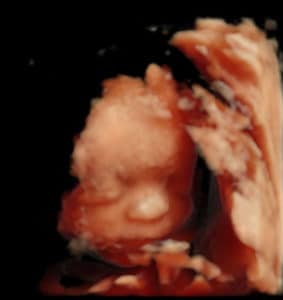

Four Chemical Pregnancies, Now My Keeper!

Good Things Take Time!

four-chemical-pregnancies-now-with-keeperI got pregnant after 4 chemicals.

I had my tubal reversal done on December 20th 2017.

I am so excited and grateful for Dr. Monteith and his staff.

Patient age: 35

Tubal ligation type: Resection (tied or cut)

Patient hometown: Wilmington, North Carolina